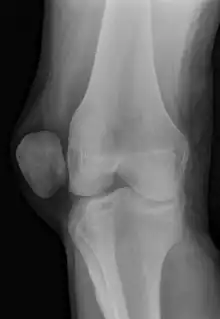

| X-ray showing a patellar dislocation, with the patella out to the side. | |

A patellar dislocation is a knee injury in which the patella (kneecap) slips out of its normal position.[5] Often the knee is partly bent, painful and swollen.[1][2] The patella is also often felt and seen out of place.[1] Complications may include a patella fracture or arthritis.[3]

A patellar dislocation typically occurs when the knee is straight and the lower leg is bent outwards when twisting.[1][2] Occasionally it occurs when the knee is bent and the patella is hit.[1] Commonly associated sports include soccer, gymnastics, and ice hockey.[2] Dislocations nearly always occur away from the midline.[2] Diagnosis is typically based on symptoms and supported by X-rays.[2]